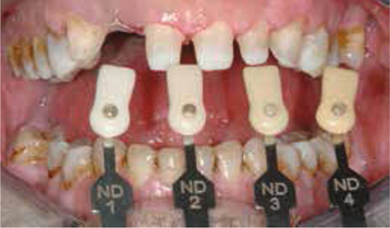

Tijdelijke fase (november en december 2010)

In de tijdelijke fase begonnen we met het vervaardigen van een mock-up in het front om de lengte van de nieuw frontelementen te bepalen (afbeelding 16 ). Tevens voerden we een esthetische facebow en beetbepalingen uit. Ook werden de esthetische en fonetische checklists ingevuld. Hiervoor gebruikten we de lijsten zoals die zijn opgesteld door Mauro Fradeani. Deze lijsten worden bij zijn boek The esthetic rehabilitation in fixed prosthodontics - vol 1 geleverd. Al deze informatie werd, samen met de overige informatie uit de aanvullende onderzoeken en met een paar nauwkeurige afdrukken (Impregum, 3M Espe) aan de tandtechnicus gegeven voor het vervaardigen van een set-up in was (afbeelding 17 en 18 ) en de bijbehorende mallen.

Met behulp van de mallen kan de set-up in was naar de mond worden overgebracht voor de zogenaamde test-drive. Dit werd gedaan met behulp van Protemp 4 (3M Espe). Na het aanbrengen van Wedjets (Coltene Whaledent) om de interdentale ruimtes open te houden ten behoeve van de interdentale reiniging (afbeelding 19 en 20 ), werden alle elementen gezandstraald, geëtst, waar nodig geprimed en gebond. Vervolgens vulden we de mallen met de kunsthars en brachten deze aan op de elementen. Na het verwijderen van de overmaat (afbeelding 21 )en het bijwerken van de randen werd de modelsituatie overgebracht in de mond (afbeelding 22-26 ). Met deze voorziening kan de patiënt relatief zorgeloos gedurende langere tijd functioneren. Deze tijdelijke fase geeft de mogelijkheid om de samen met de tandtechnicus de ontworpen voorziening te testen op esthetiek en functionaliteit en waar nodig aan te passen.